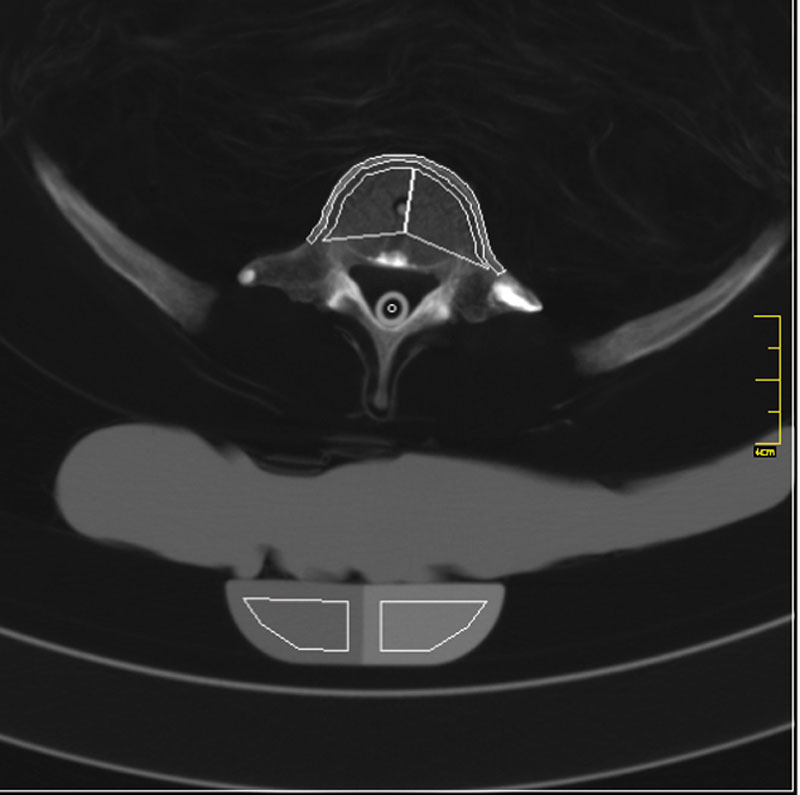

Röntgenphantom Hüfte, transparent

Unsere weltweit einmaligen Röntgenphantome enthalten echte menschliche Skelett - Teile. Dies gewährleistet erstklassige Aufnahmen und realistische Übungsbedingungen. Eine praxisnahe Röntgen - Ausbildung ist ohne diese Modelle nicht möglich. Jedes Modell wird in handwerklicher Einzelstückfertigung hergestellt und ist jeweils ein Unikat. Bedingt durch die Verwendung von echten Knochen und die individuelle Fertigung weichen die einzelnen Modelle in Größe und Beschaffenheit voneinander ab. Ausführung transparent! Abbildung zeigt Modell 7245, Opak-Ausführung!

7240

7.016,81 € (8350,00 €)

7245

Röntgenphantom Hüfte, Opak

6.949,58 € (8270,00 €)